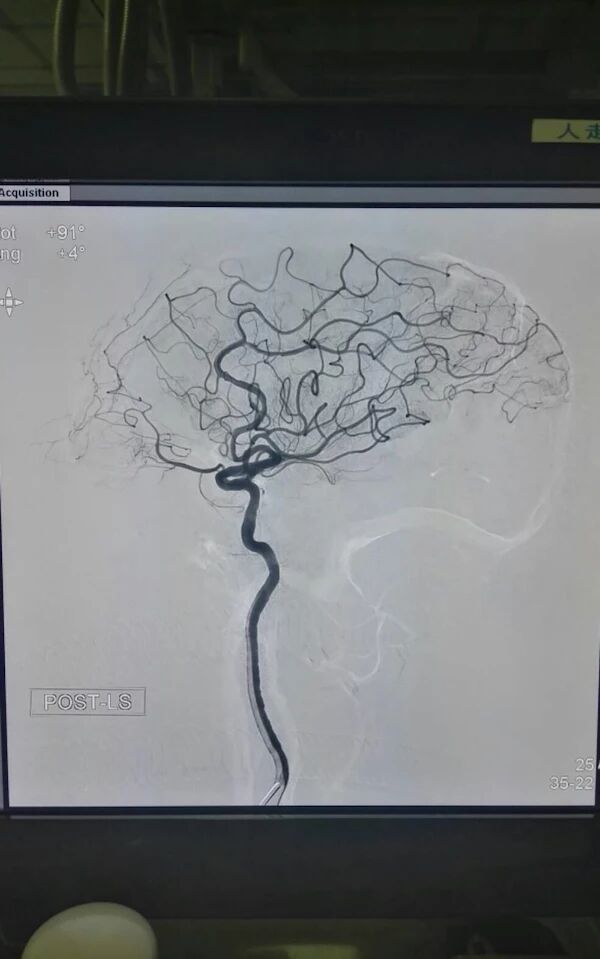

术前脑血管造影显示左侧大脑中动脉急性闭塞,代偿不佳

微导管通过血栓后造影显示远端血管通畅

使用ReviveSE取栓,一次成功

术后观察30分钟,达到2b级血流,近分叉部的狭窄二期处理,细小下干未进一步取栓!回病房给予替洛菲班和复合量双抗治疗